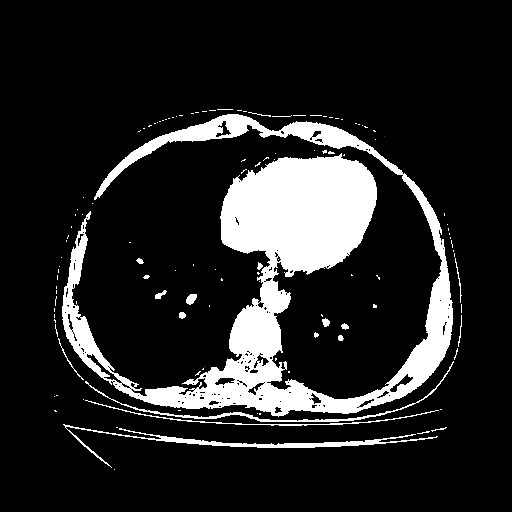

Original NATIVE CT scan (input)

Full window (WL 1023.5, WW 4095 β†’ Low βˆ’1024, High +3071)

Actual HU range: [-1024.0, 3071.0]